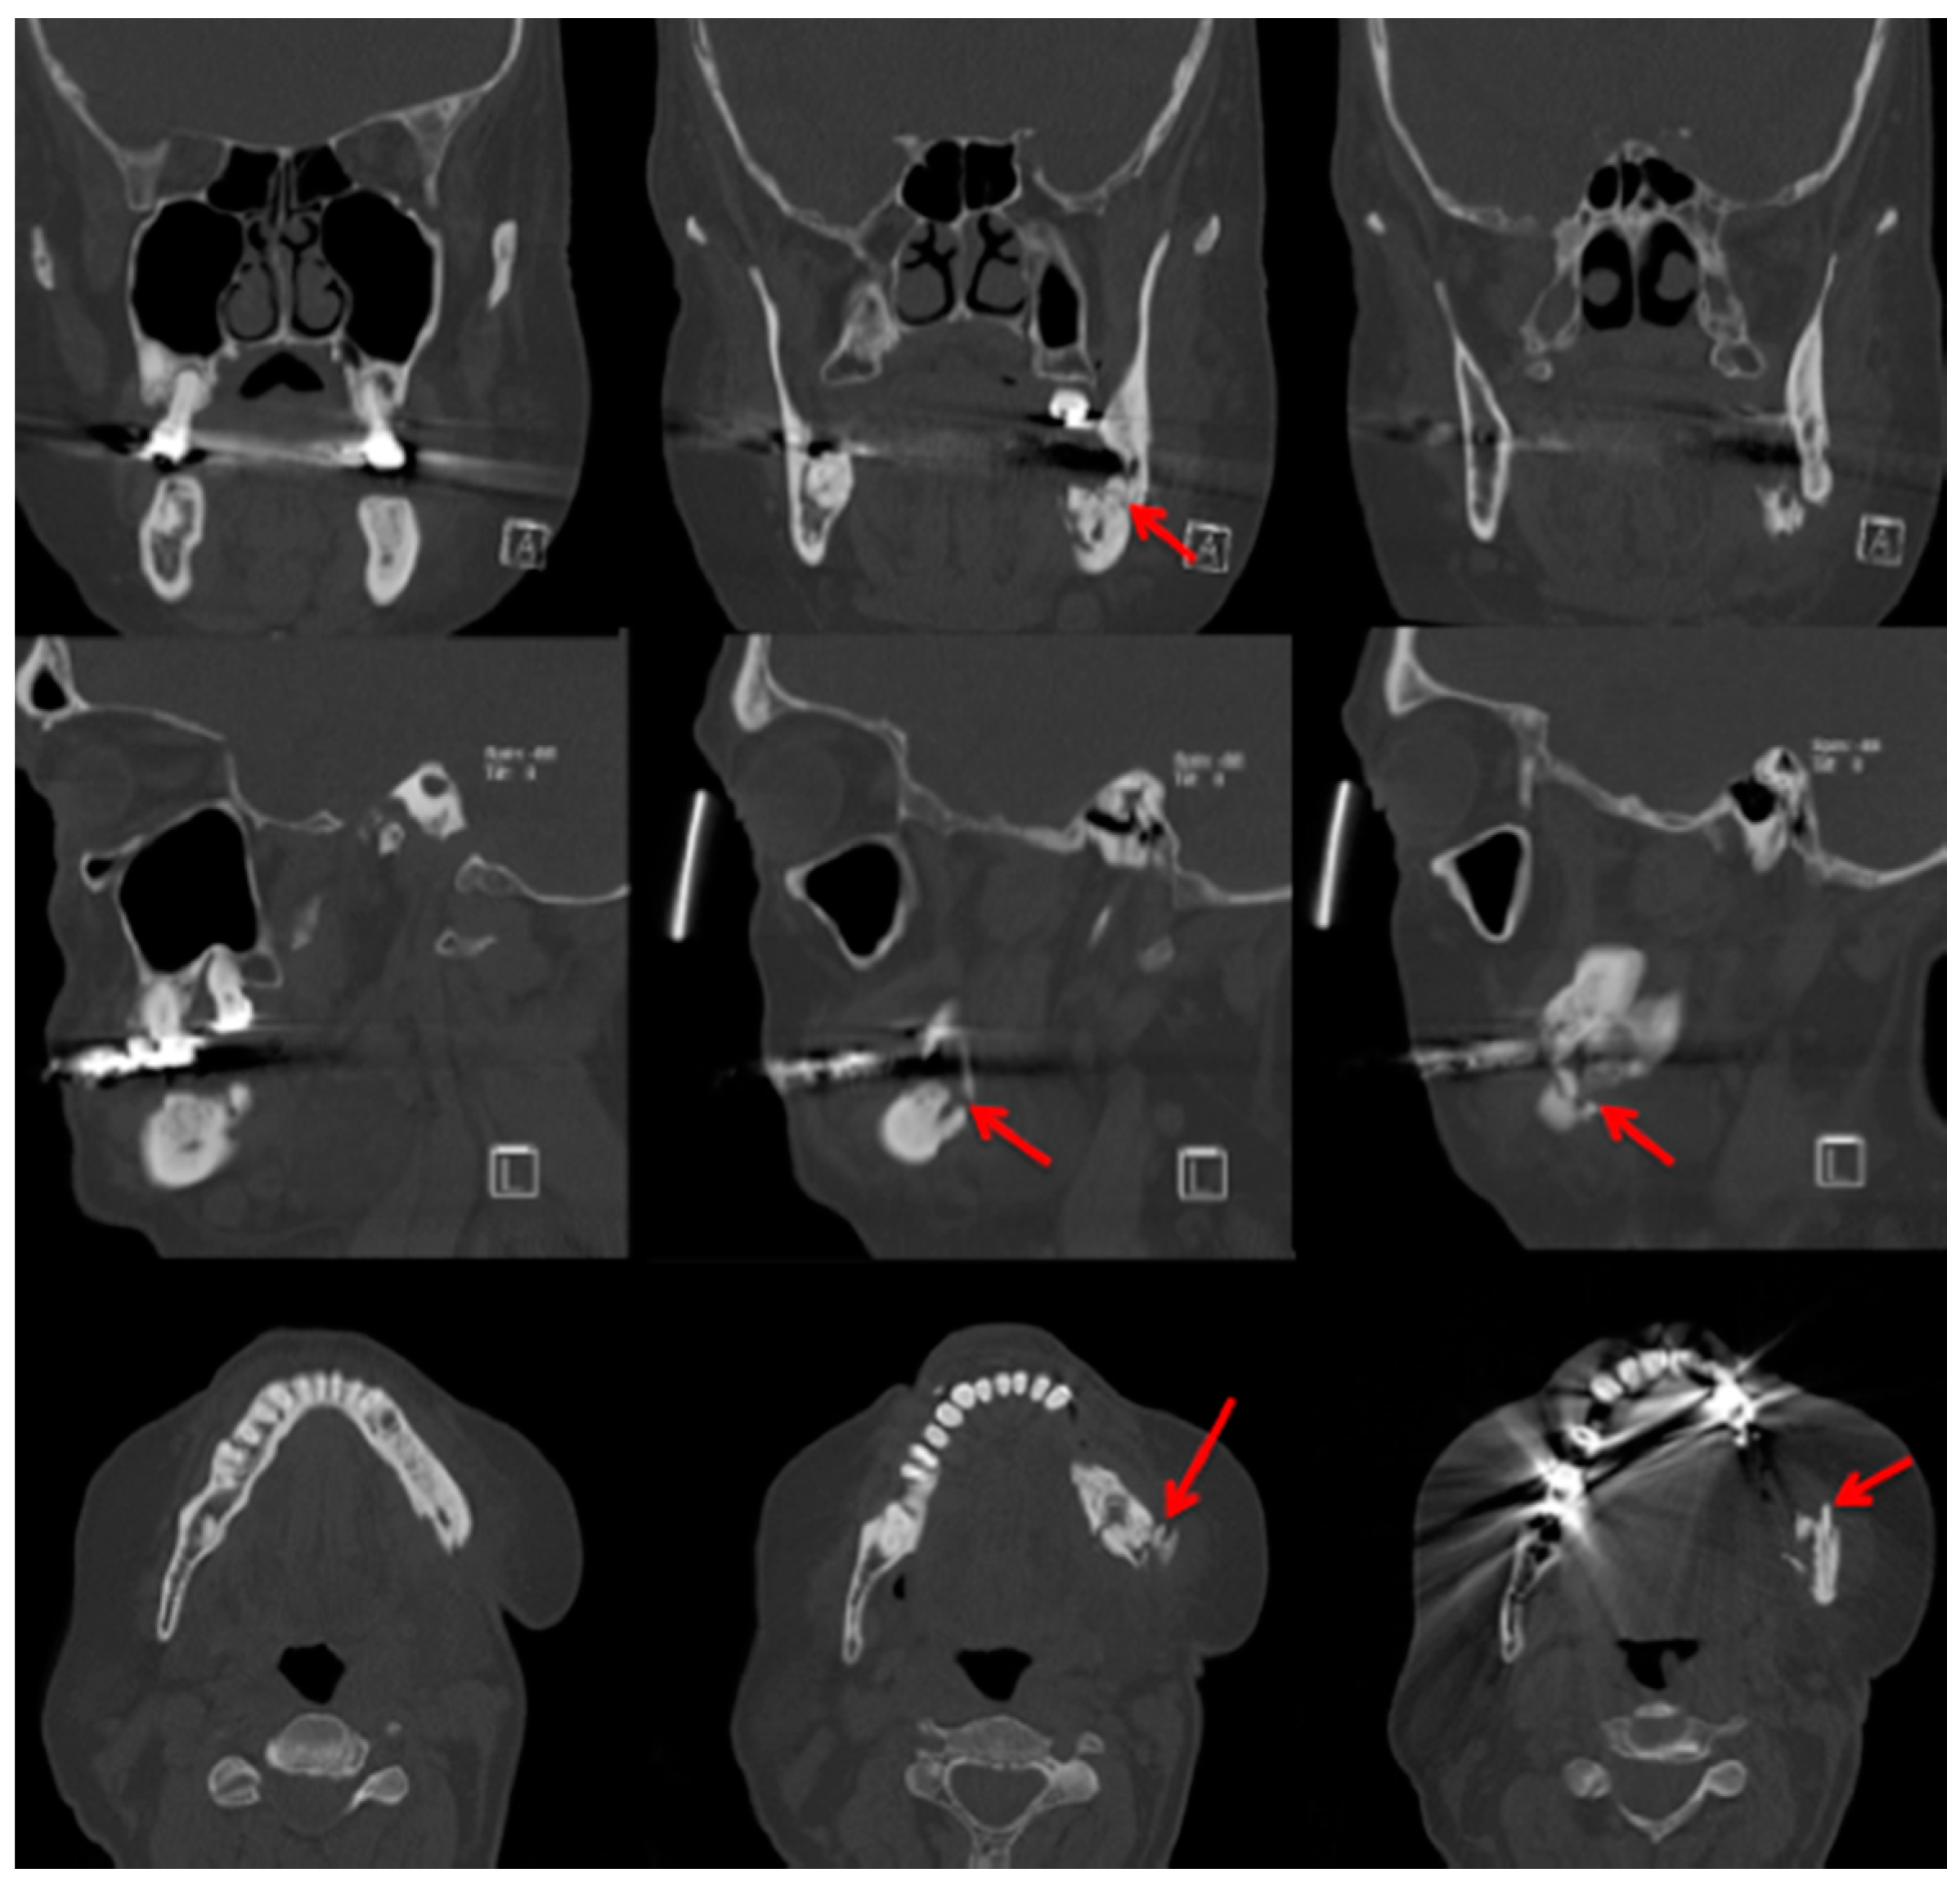

In comparison with MRI and CT, there are fewer papers about imaging of MRONJ with CBCT [23]. Before Torres et al. investigated mandibular inferior cortical bone thickness [16], they studied cortical bone dimensional changes in MRONJ patients using CBCT data sets. By assessing the data sets (12 patients/66 test persons) using three different techniques, they could show that “the cortical bone measurements were significantly higher in cases than controls for all 3 techniques” [24]. As stated in Yalcin and Gungormu’s review, typical findings in CBCT and CT are “pathologic fractures, narrowing of the marrow space and involvement of the inferior alveolar canal” [23]. Figure 4 shows a patient with narrowing of the marrow space and sequestra from our clinical database.

Figure 4.

Cone-beam computed tomography (Carestream CS 9300) Patient: 77 years old, metastatic prostate cancer, ibandronic acid and later another antiresorptive drug: denosumab. For panoramic radiograph see Figure 2. 1st row: coronary view; 2nd row: axial view; and 3rd row: sagittal view. Red arrows: sequester; blue arrows: sclerotic region. AAMOS staging: stage 2.

Detecting periosteal thickening or bone density changes at an early stage before it gains clinical importance might be another case [23,25] for the use of CBCT. Wilde et al. stated that the two most common findings in CBCT for MRONJ are “destruction of the trabecular structure of the cancellous bone and erosion of the cortical bone” [26]. The authors retrospectively assessed 27 CBCT scans from MRONJ patients, and aspects of “sclerotic manifestations” were discussed. Contrary to Olutayo et al. [27] they did not find a correlation between sclerotic manifestation and the severity of the MRONJ [26]. Treister et al. described CBCT as superior at detecting fragmentation and sequestra in comparison to panoramic radiographs [28]. In our examples (Figure 1 panoramic radiograph and Figure 4 CBCT scan) the extent is visible in both modalities but more detectable in the CBCT scan. Guggenberger et al. found that CBCT imaging and clinical examination showed less extensive changes than positron emission tomography (PET)/CT and MRI [29]. A model using CBCT scans was developed by Barragan-Adjemian et al. [30]. Based on their observations, they found an explanation of how an exposed sequestra develops. In detail, their model describes, “the formation of a necrotic body (or bodies) or involucrum(s) inside the trabeculae in sclerotic mandibular bone. The involucrum most likely represents dead bone that becomes surrounded by a resorptive circumference that increases with time.” [30]. Additionally, “the involucrum follows the path of least resistance (which is the easiest and quickest means to remove the necrotic body either lingual or towards the edentulous area) leading to an exposed sequestrum (clinical ONJ) or, alternatively, if the tooth is missing moves towards the edentulous area.” [30]. Since Cankaya et al. [31] found in their rat model that “the extent of the BONJ lesions assessed from CBCT scans did not differ significantly from the intraoperative situation, and a significant correlation between CBCT measurements and intraoperative measurements was found” [31], and radiation dosage a low as just 3 μSv (effective dose 5 × 5 cm adult exam) are commercially published [32], CBCT might gain even greater relevance in the future.